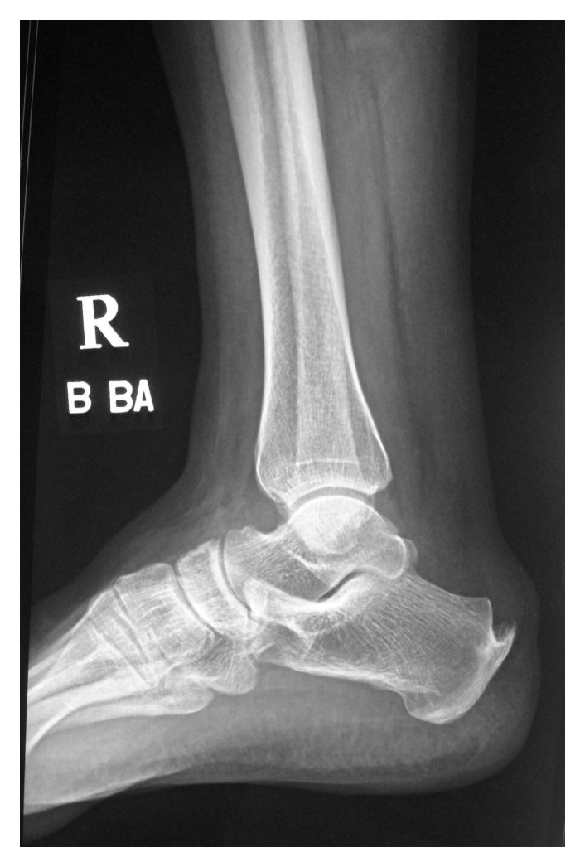

- 跟骨骨刺:是足跟部位骨头上的骨刺,通常是由于长期受力或损伤引起的。

足跟痛是指足跟部位出现的疼痛,这是一种常见的足部疾病,很多人都会经历。足跟痛的病因很多,包括以下几种情况:

- 足底筋膜炎:是足底筋膜受到过度拉伸或磨损引起的一种炎症,常见于长时间走路或站立的人群。

- 跟腱炎:是跟腱发生炎症引起的疼痛,通常是由于过度使用脚后跟所致。

- 跖骨骨折:是足底骨骼中的一种骨折,通常是由于跌倒或受到重击引起的。